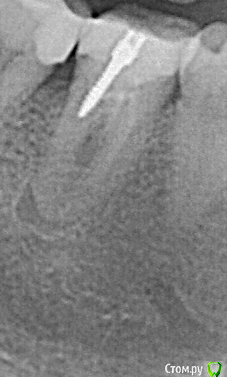

apex007 Опубликовано 22 апреля, 2016 Поделиться Опубликовано 22 апреля, 2016 Добрый вечер! Перелечивали каналы в резорциновом 46 из-за образования небольшой кистогранулемы в апикальной части. Корни у апекса изогнутые в сторону вертикальной оси зуба, поэтому пройти каналы полностью (до апекса) не удалось. Каналы закрыты гуттаперчей. Врач предлагает установить культевую вкладку, но отказывается делать рентген. Разве не нужно делать контрольные снимки в таком случае? Или здесь по принципу "уже ничего не сделать, поэтому и смысла нет"? КТ до лечения есть, могу выложить.Спасибо! Ссылка на комментарий

apex007 Опубликовано 27 января, 2021 Автор Поделиться Опубликовано 27 января, 2021 Всем ответившим большое спасибо за помощь, для истории выкладываю снимки до перелечивания () и через 4 месяца (улучшение, ). Ссылка на комментарий